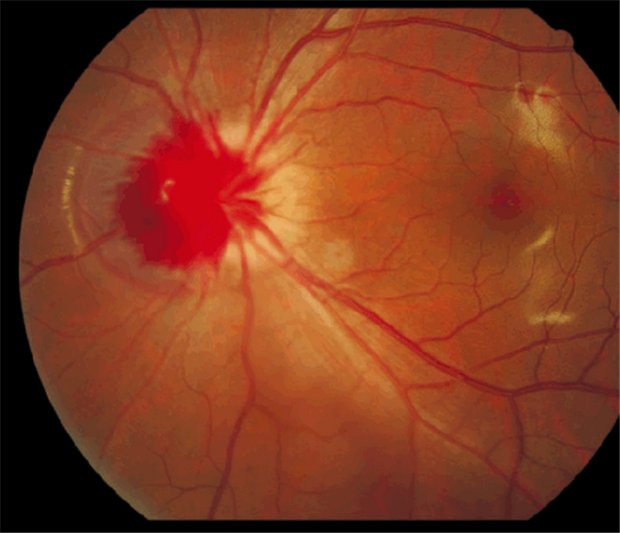

1、外眼正常,以眼底镜检查可(kě)见玻璃體(tǐ)混浊,视网膜上有(yǒu)出血。

3、如果出血量多(duō)或反复出血,血液进入玻璃體(tǐ)内引起玻璃體(tǐ)混浊,形成增殖性玻璃體(tǐ)视网膜病变,如糖尿病视网膜出血等,视力就会受到严重损害,甚至失明。这也是眼底出血危害。

5、引起诸多(duō)严重的并发症,如黄斑病变,新(xīn)生血管性青光眼、玻璃體(tǐ)积血、视神经萎缩、增殖性视网膜病变、牵拉性视网膜脱离,如不及时有(yǒu)效的,常可(kě)导致失明。